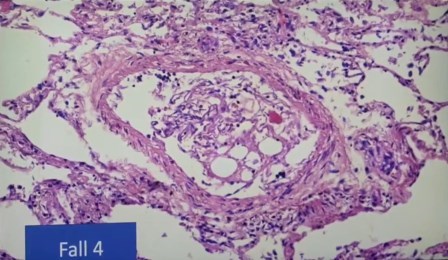

Atelectasis, pulmón colapsado

Aglomeración de linfocitos alrededor de un vaso

Esta aglomeración está en investigación

Vasos y endotelios, también en investigación, debido a la rareza, que les impide determinar lo que es

Esto no se pudo interpretar, son cosas “rarísimas” en este pulmón, y no solo una, sino varias veces, es decir, en varios fallecidos.

“Esto tampoco se que es, no tengo idea, no es un nervio, creo que es un vaso”, indica.